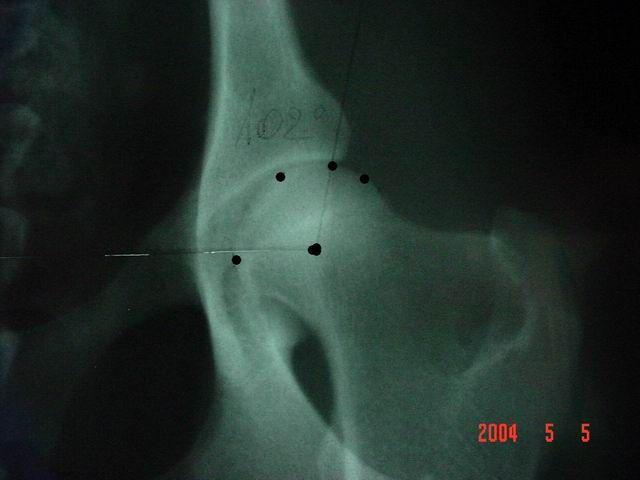

Kattintás=nagyításEnyhe fokú a dysplasia, ha az ízületi rés kissé kiszélesedett divergáló, a vápa laposabb, a combcsontfej nem teljesen szabályos kör alakú, a szög 100° körüli. Enyhe gyulladásra utaló tünetek előfordulhatnak (Morgan-vonal, scleroticus gyűrű, elülső vápakontúron felrakódás).